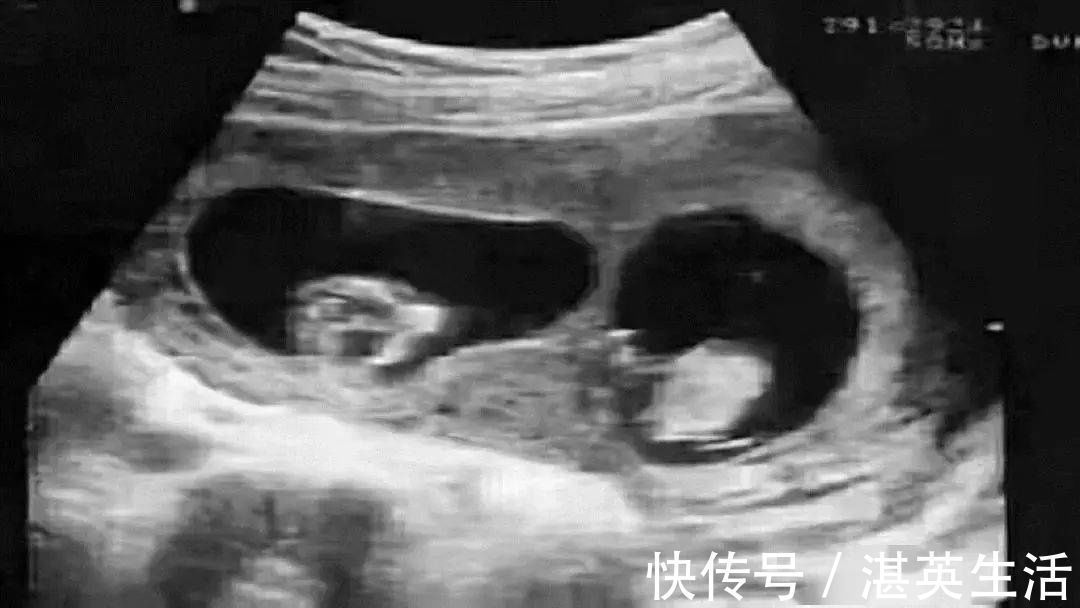

广医三院法医物证司鉴所马晓燕:这可能就遇到了鉴定行业中非常罕见的嵌合体案例,也就是说,这位“爸爸”身体内携带有两个人的DNA,可能他在妈妈肚子里的时候,还有一个双胞胎弟弟,但是这个双胞胎弟弟的胚胎没有发育下来,反而和他的胚胎出现了融合,导致这个“爸爸”携带两个人的DNA出生,而且他把弟弟的DNA传给了孩子。

嵌合体,是发生在动物生殖发育领域的一种特殊现象,也叫喀迈拉现象。喀迈拉是希腊神话中的喷火怪兽,身体由狮子、山羊和毒蛇构成。简单来说, 嵌合体就是两颗受精卵融合在一起并最终成长为一个单独的个体,在高等动物中并不常见。据统计,现在全球总共只有30例左右嵌合人。

说得通俗一点就是,一个人在她/他还是一个受精卵的时候,同时还存在另外一个受精卵,也就是双胞胎。但是另外一个受精卵太弱了被他自己这个受精卵吃掉合并,因为免疫耐受的原因,这个被吃掉的受精卵并没有完全消失,一部分的基因在身体里得以存活下来,并且在日后的生长发育的过程中还可以表达自己的基因组。